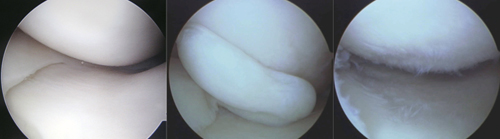

左:正常な半月板 中央:陥頓した半月板 右:部分切除後